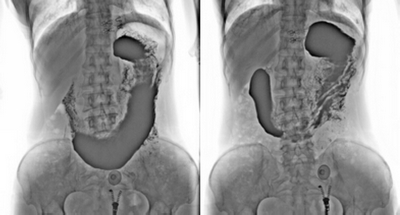

3. 數字化胃腸:

★消除普通數字胃腸機視野小的缺陷,直接獲得大視野全數字化圖像 (17x17) 。

★更加方便胃腸、食管、上消化道、全消化道等造影功能!